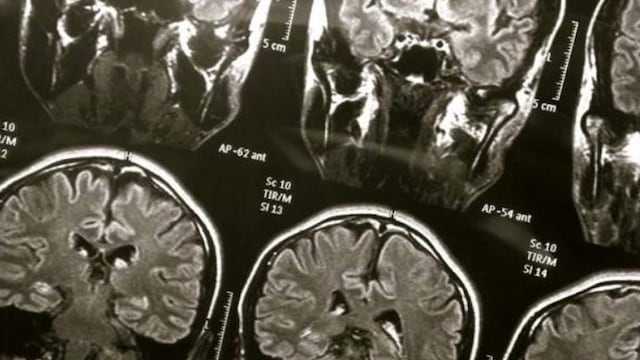

Tras el comienzo del Covid-19, médicos de todo el mundo comenzaron a notar una serie de efectos persistentes en algunos pacientes, mucho después de haberse recuperado. Dichos malestares iban desde fatiga, pérdida de memoria, confusión y otras anomalías. Los profesionales de la salud los llamaron "niebla cerebral" o "cerebro coronavirus".

Pero hasta el momento era un misterio lo que la originaba. Por ese motivo, un grupo de investigadores han publicado en Cancer Cell sus resultados a un estudio sobre líquido cefalorraquídeo que arrojó una pista importante sobre el inicio de la "niebla cerebral".